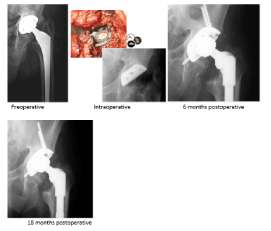

Case 5 - Paprosky Type 3a

Case description / anamnesis: 68-year-old male

Left acetabular cup mobilization 8 years postoperative (figure 9).

Figure 9. Case 5 - Paprosky Type 3a

Defects were characterized by moderate-to-severe destruction of the acetabular walls and posterior column, rendering these structures non-supportive. The hip center migrates super-lateral (up-and-down deformity)

Treatment (figure 10):

Figure 10. Case 5 - Paprosky Type 3a - Treatment

Old cup was removed.

20cc ReadiGraft BLX Putty was mixed with 60cc of cortical/cancellous chips to fill the bone void.

Cup and screws and cemented cup replaced.

Outcomes:

Postoperative course was uneventful and at 8 months postoperative the cup was completely integrated in the bone.